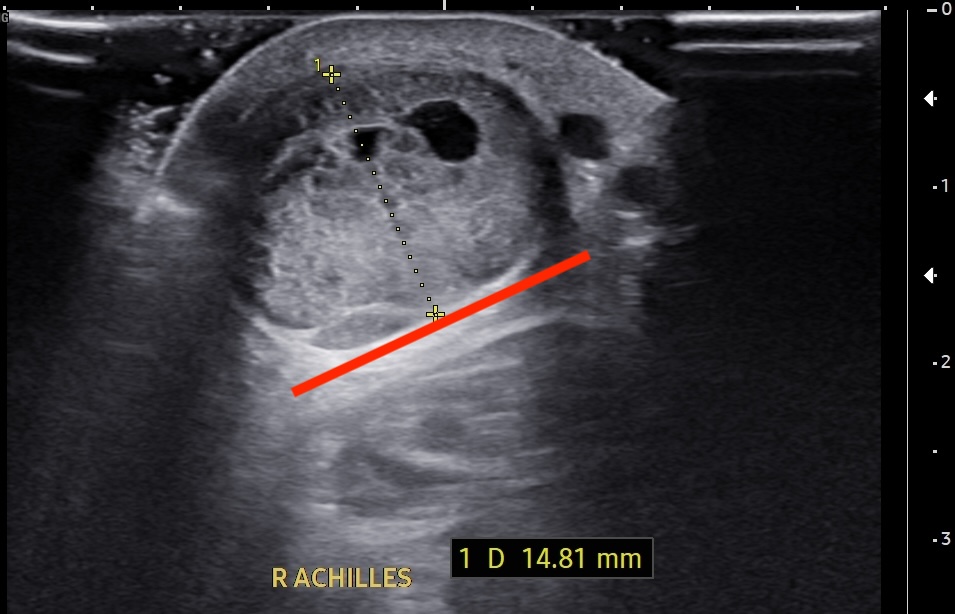

Short-axis ultrasound image of the midportion Achilles tendon showing the depth and width of the largest intrasubstance partial tear.

Short-axis ultrasound image of the midportion Achilles tendon showing the tendon thickness measurement.